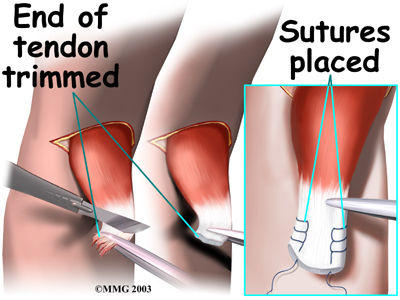

Attention is given to the . A scalpel is used to slice off the damaged and degenerated end. Sutures are then crisscrossed through the bottom inch of the distal biceps tendon.

A curved instrument is passed through the incision and directly between the radius and ulna bones. The surgeon pushes the instrument through this space, puncturing the muscles and soft tissues. The surgeon feels the back side of the forearm for the spot where the instrument is protruding. A is made at this spot.

The original attachment on the radius, the radial tuberosity, is . An instrument called a burr shaves off the surface of the tuberosity. The burr is then used to create a small cavity in the bone for the tendon to fit inside. Three small holes are drilled into the top of the rim of bone to secure the sutures.

The tendon is passed between the radius and ulna, exiting through the second incision that was made on the back of the forearm. The sutures are threaded into the three holes that were drilled into the rim of the radial tuberosity. The surgeon ties the sutures, securing the . When the surgeon is satisfied with the repair, the skin incisions are closed, and the elbow is placed either in a cast or a range-of-motion brace.